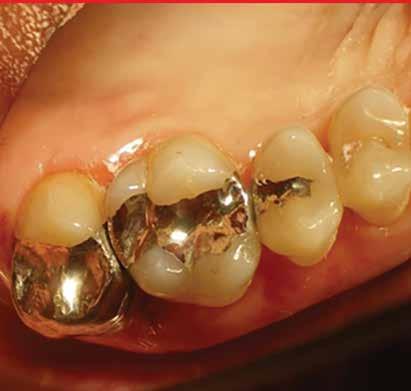

MarchApril 2026 ISSUU by Florida Dental Association - Issuu